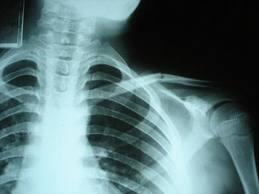

Esta práctica es totalmente nociva según los investigadores que afirman que este tipo de técnicas deberían utilizarse solo en casos de fracturas o lesiones graves, que jamás sería algo conveniente someter a un paciente que no sufre una lesión importante a este tipo de exámenes.

Estos resultados hacen referencia al clásico dolor lumbar consultado por el paciente que afirma que constantemente se somete a radiografías para hacer un control de su situación a través de imágenes, según los investigadores se estaría sometiendo a la radiación a la personas si las sesiones de radiografía son repetidas.